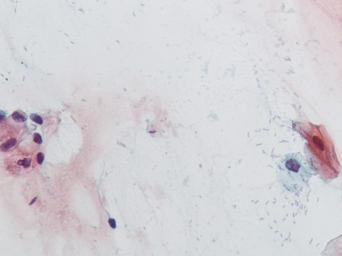

Keywords: lesión intraepitelial escamosa de bajo grado lesiónintraepitelialescamosadebajogrado citología de cuello uterino citologíadecuellouterino citología exfoliativa ginecológica citologíaexfoliativaginecológica citología de cribado citologíadecribado citología anatomía patológica anatomíapatológica bethesda 2001 bethesda2001 osuna cérvix uterino cérvixuterino hpv españa screening lsil enfermedades de transmisión sexual enfermedadesdetransmisiónsexual imágenes de citología ginecológica imágenesdecitologíaginecológica papanicolaou test de papanicolaou testdepapanicolaou tinción de papanicolaou tincióndepapanicolaou Células con núcleo y citoplasma aumentado de tamaño, núcleos irregulares, como plumosos, tendencia al color naranja de muchas células, halos en algunos casos, núcleos dobles en otros, algunos núcleos hipercromáticos. Células con núcleo y citoplasma aumentado de tamaño, núcleos irregulares, como plumosos, tendencia al color naranja de muchas células, halos en algunos casos, núcleos dobles en otros, algunos núcleos hipercromáticos.